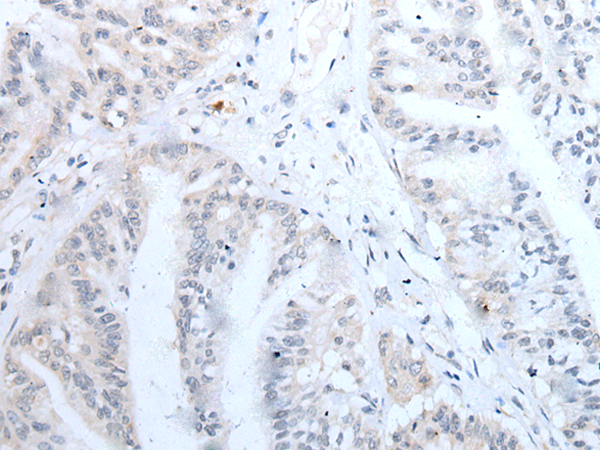

分类: 科研抗体货号: P12772别名: NAG14; NGL-2应用: IHC反应种属: Human, Mouse, Rat